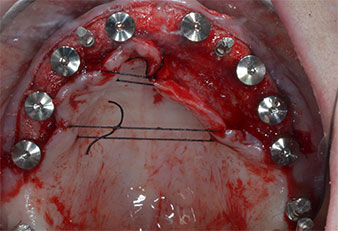

Fig. 1: Vista preoperatoria del borde maxilar, con las posiciones del implante marcadas con la ayuda de una plantilla quirúrgica de plástico. Debido a la baja altura del borde, se planificaron implantes posteriores supercortos.

Fig. 2: Después de la incisión en la zona crestal media y de la preparación de colgajos mucoperiósticos, las posiciones del implante se transfirieron al hueso.

Debido al hueso relativamente duro (D2) existente en el sector anterior, los sitios de los implantes largos de 10 mm de las posiciones 11 y 21 se finalizaron con una fresa rotatoria de 4 mm de diámetro, en combinación con un contra-ángulo quirúrgico WS-75 L de W&H, el motor de implantes Implantmed de W&H y el módulo opcional Osstell ISQ de W&H. En cambio, debido a la existencia de hueso blando, los sitios posteriores se prepararon hasta un diámetro final de 3 mm utilizando el inserto Piezomed I3P. Por último, los implantes se colocaron a nivel crestal para su osteointegración durante tres meses (figuras 6-10). La prótesis existente se mantuvo sobre cuatro implantes provisionales (figura 8).

Implante en el nivel de tejido de 10 mm

Fig. 6: En la posición 21 se colocó un implante en el nivel de tejido de 10 mm. El implante de la posición 11 y los tres implantes posteriores izquierdos de 4 mm ya estaban colocados en su lugar.